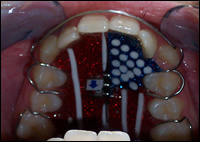

Fig 3 & 4: Upper and lower Schwartz Appliances were fabricated.